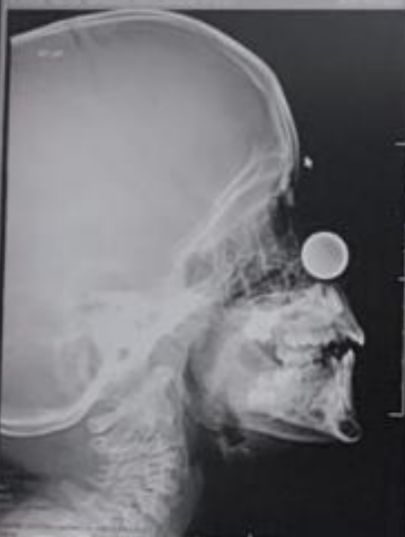

استخراج قطعة معدنية نقدية من أنف طفل السبع أعوام

تمكن فريق طبي بمستشفى حراء العام عضو تجمع مكة المكرمة الصحي ، من إستخراج قطعة نقدية معدنية من أنف طفل يبلغ من العمر 7 سنوات كانت قد دخلت إلى أنفه عن طريق الخطأ ولم تظهر عليه أي أعراض على الإطلاق أو ضيق في التنفس ، وفور وصول الطفل لقسم الطوارئ تم عمل الإجراءات اللازمة وعمل الأشعة اللازمة وتبين وجود جسماً غريباً داخل الأنف وقرر الفريق الطبي القيام بالتدخل الفوري لإنقاذ حياة الطفل وبعد عدة محاولات تم إستخراج العملة المعدنية بدون أي عملية جراحية حيث استغرق الإجراء ما يقارب 20 دقيقة ، وبفضل من الله ثم جهود الكادر الطبي المعالج والتدخل السريع، تم استخراج هذه العملة المعدنية من الطفل دون أي مضاعفات تذكر وخرج من المستشفى وهو بحالة جيدة ومستقرة ولله الحمد والجدير بالذكر بأن قسم الطوارئ بمستشفى حراء قد باشر الكثير من الحالات المشابهة حيث يعتبر إدخال جسم غريب عن طريق الأنف أو الفم مشكلة كبيرة ، خصوصاً في فئة الأطفال من عمر 6 أشهر إلى 3 سنوات ، لما قد تؤدي له من مضاعفات خطيرة وحالات إختناق قد تصل إلى الوفاة لا سمح الله .